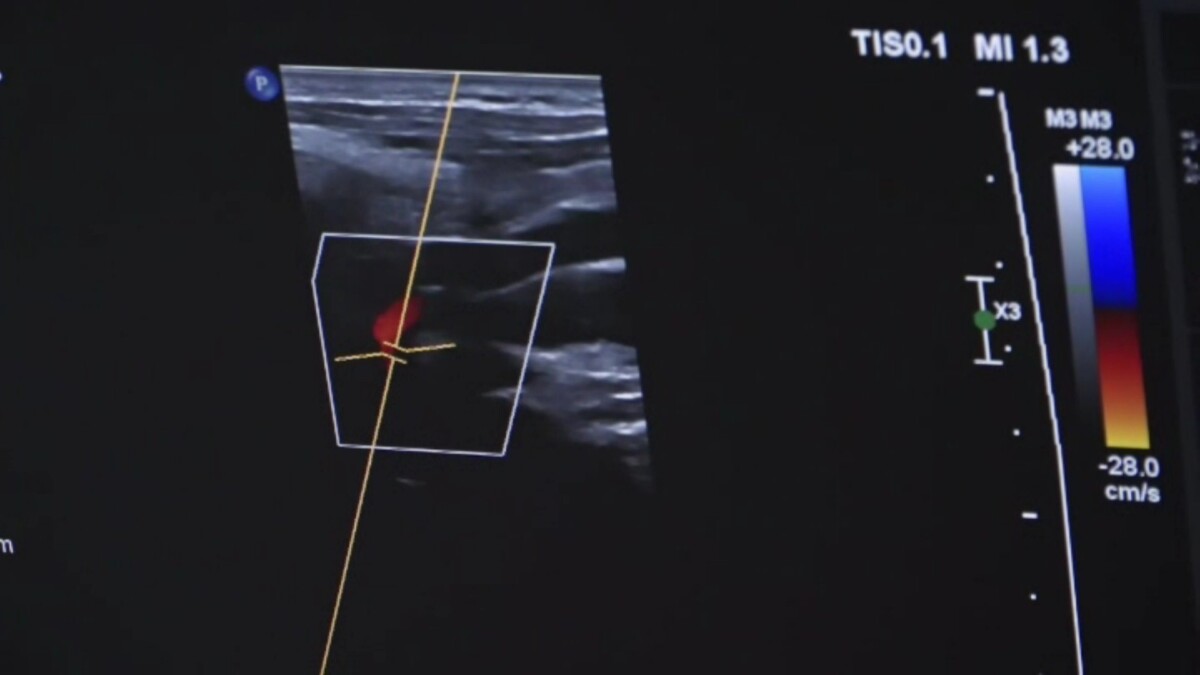

彰化醫院急診洪子文醫師指出,魏女士到院後經電腦斷層檢查,腦部無異常,僅後腦有撞傷,後續轉神經內科做頸動脈超音波、腦波及24小時心電圖檢查,也未發現心臟或腦部問題。魏女士表示,醫師提醒她平日注意情緒控制,之後就未再發生昏厥。